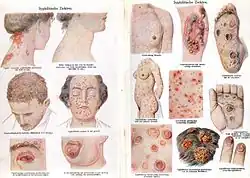

- Syphilis is an STI caused by a bacterium. Untreated, it can lead to complications and death.[67] Clinical manifestations of syphilis include the ulceration of the uro-genital tract, mouth or rectum; if left untreated the symptoms worsen. In recent years, the prevalence of syphilis has declined in Western Europe, but it has increased in Eastern Europe (former Soviet states). A high incidence of syphilis can be found in places such as Cameroon, Cambodia, Papua New Guinea.[68] Syphilis infections are increasing in the United States.[69]